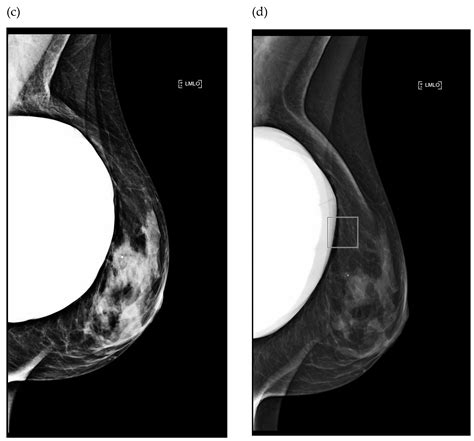

A mammogram is a specialized medical imaging procedure that uses low-dose X-rays to detect potential issues within breast tissue. Because the quality of these images is paramount for early detection, certain factors can inadvertently interfere with the clarity of the scan. These factors often stem from what you choose to wear or apply to your skin in the hours leading up to the appointment. By taking a few simple, intentional actions on the night before mammogram, you create the best possible conditions for a successful and efficient screening.